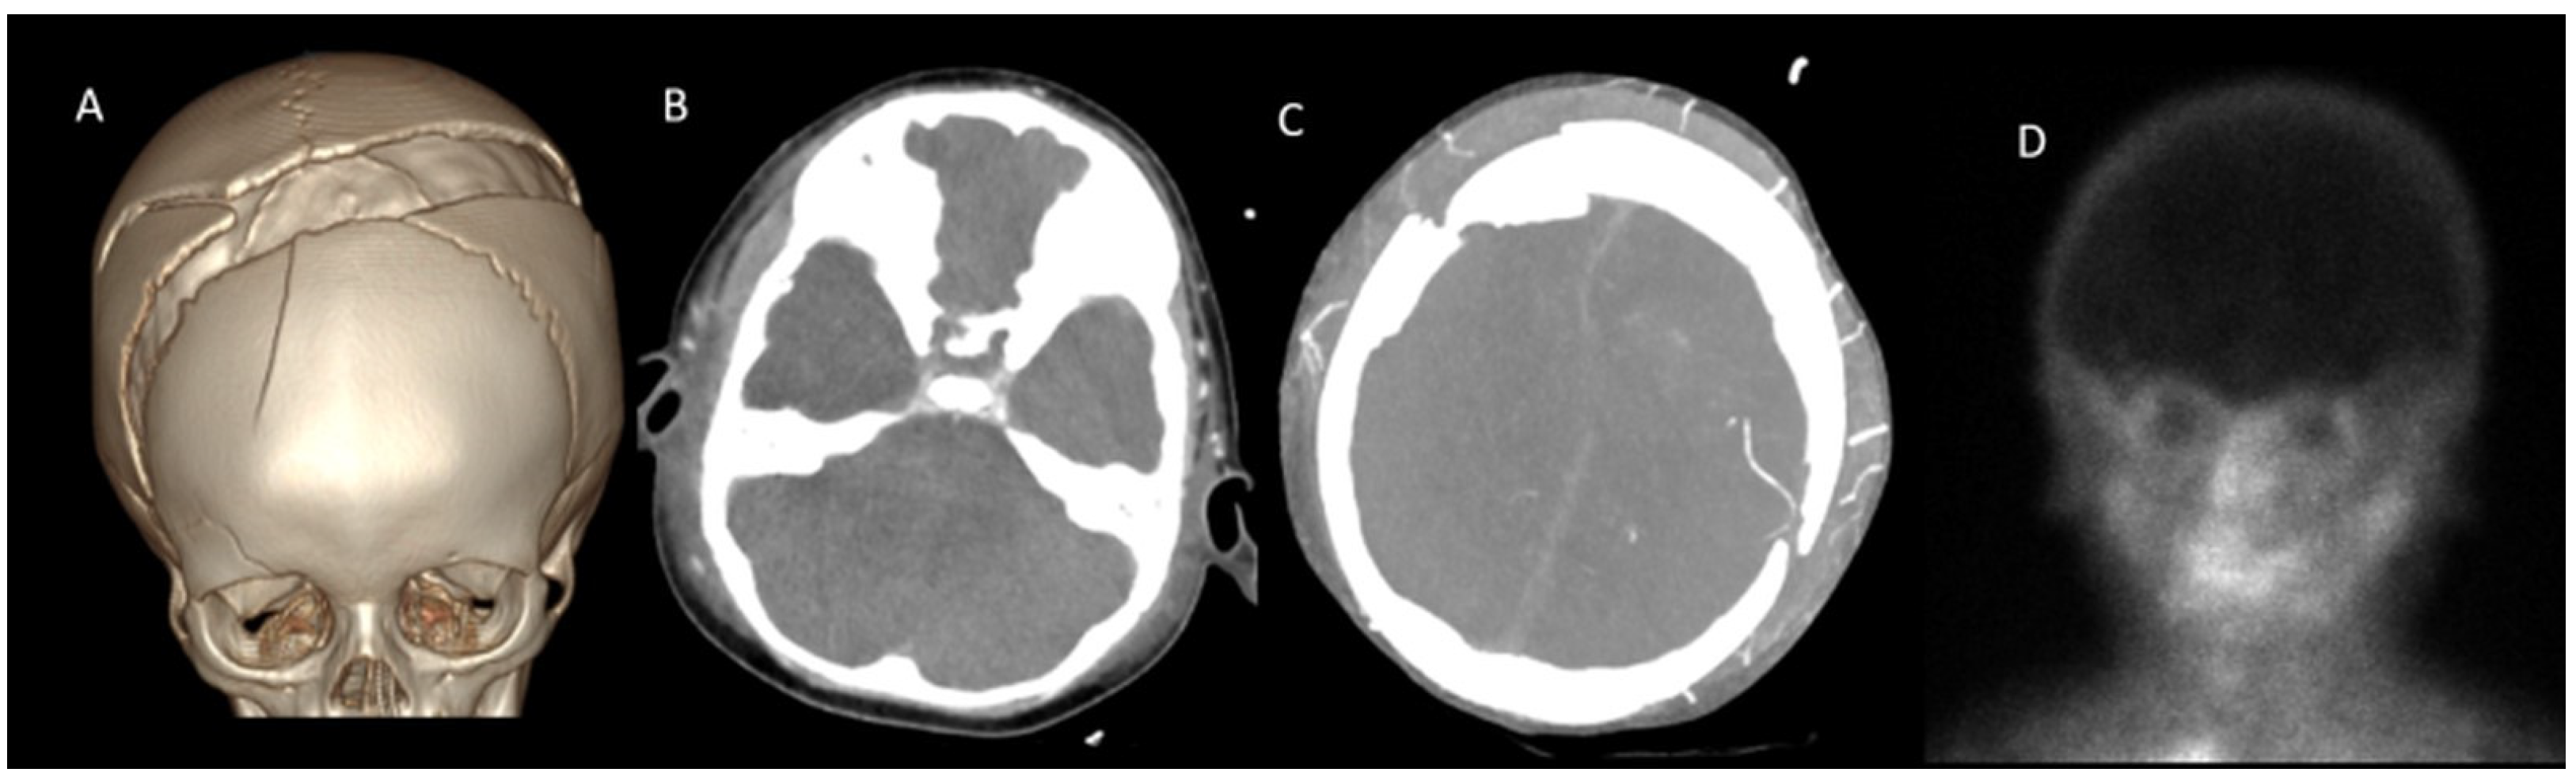

- A60-V60: Absence of opacification in M4 branches of the middle cerebral arteries (MCAs) and ICVs in the venous phase, based on the reference 4-point system by Frampas et al. [11].

- A20-V60: Absence of opacification in M4 branches of the MCAs in the arterial phase and ICVs in the venous phase, based on the revised arteriovenous scoring system by Nunes et al. [12].

- ICV-SPV: Absence of opacification in the ICVs and SPVs in the venous phase, based on the revised venous scoring system by Marchand et al. [10].

| Open Fontanel | 12 (27.9) |

| Craniectomy | 2 (4.7) |

| Fracture | 5 (11.6) |

| Shunt | 5 (11.6) |